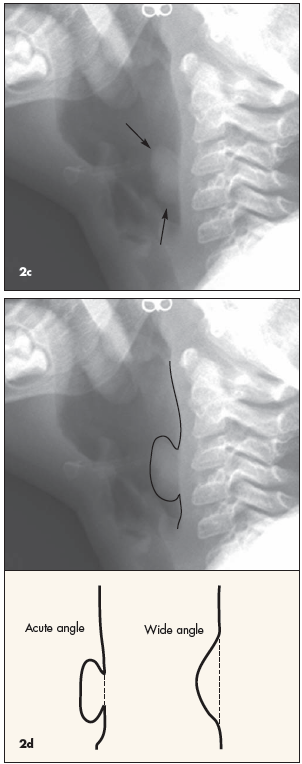

Croup. Because it is summer, croup is unlikely. In any event, the long, smooth, steeple-like narrowing of the subglottic airway that is characteristic of croup is not evident. (Figure 2b shows signs of croup in a different patient.)

Mass. This is the correct answer. On the lateral view, a lobulated soft tissue mass can be seen arising from the posterior wall of the upper hypopharynx (Figure 2c). The mass is approximately 2 cm cephalocaudal by 1 cm anteroposterior, and its edges form acute angles with the hypopharyngeal wall (oblique angles would be expected if this were extrinsic to the airway and deforming the hypopharynx from the outside [Figure 2d]). This mass is an unexpected and abnormal finding; its differential diagnosis includes hemangioma, polyp, granuloma, foreign body (although not in the esophagus because the mass forms acute angles with the pharyngeal wall), and papilloma.